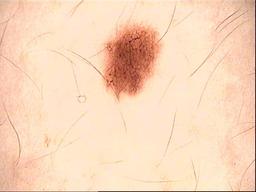

Skin lesion datasets provide essential information for understanding various skin conditions and developing effective diagnostic tools. They aid the artificial intelligence-based early detection of skin cancer, facilitate treatment planning, and contribute to medical education and research. Published large datasets have partially coverage the subclassifications of the skin lesions. This limitation highlights the need for more expansive and varied datasets to reduce false predictions and help improve the failure analysis for skin lesions. This study presents a diverse dataset comprising 12,345 dermatoscopic images with 40 subclasses of skin lesions, collected in Turkiye, which comprises different skin types in the transition zone between Europe and Asia. Each subgroup contains high-resolution images and expert annotations, providing a strong and reliable basis for future research. The detailed analysis of each subgroup provided in this study facilitates targeted research endeavors and enhances the depth of understanding regarding the skin lesions. This dataset distinguishes itself through a diverse structure with its 5 super classes, 15 main classes, 40 subclasses and 12,345 high-resolution dermatoscopic images.

Yilmaz, A., Yasar, S.P., Gencoglan, G. et al. DERM12345: A Large, Multisource Dermatoscopic Skin Lesion Dataset with 40 Subclasses. Sci Data 11, 1302 (2024). https://doi.org/10.1038/s41597-024-04104-3